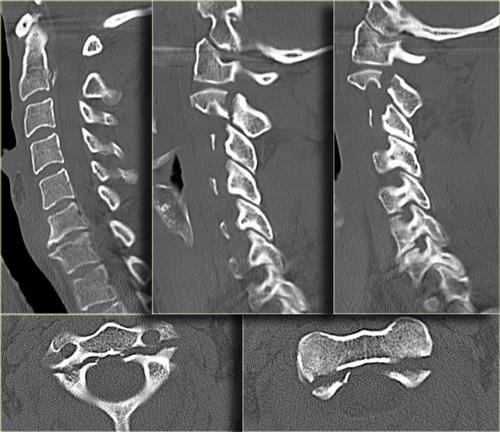

Hình bên trái là hình ảnh của một hành khách 26 tuổi không thắt dây an toàn trong vụ tai nạn giao thông, bị văng ra khỏi xe.

Bệnh nhân có nhiều tổn thương bao gồm tụ máu dưới màng cứng, tràn máu màng phổi, chảy máu ngoài màng cứng tủy sống, gãy cột sống ngực, gãy mỏm ngang L3 trái và gãy xương đòn trái.

Không có thiếu hụt thần kinh khi khám thực thể.

Các phát hiện bao gồm:

- Gãy qua nền mỏm răng

- Phù nề phần mềm trước cột sống

- Đứt dây chằng gian gai C1-C2

- Không quan sát được cột sống cổ thấp

CT xác nhận các phát hiện trên X-quang và cho thấy thêm hai phát hiện bổ sung:

- Hình ảnh qua phần bên của C2 cho thấy rõ ràng đường gãy đi qua thân C2, tức là gãy mỏm răng loại III.

-

Màng cứng phía sau ở vị trí bình thường, nhưng màng cứng phía trước bị di lệch (mũi tên).